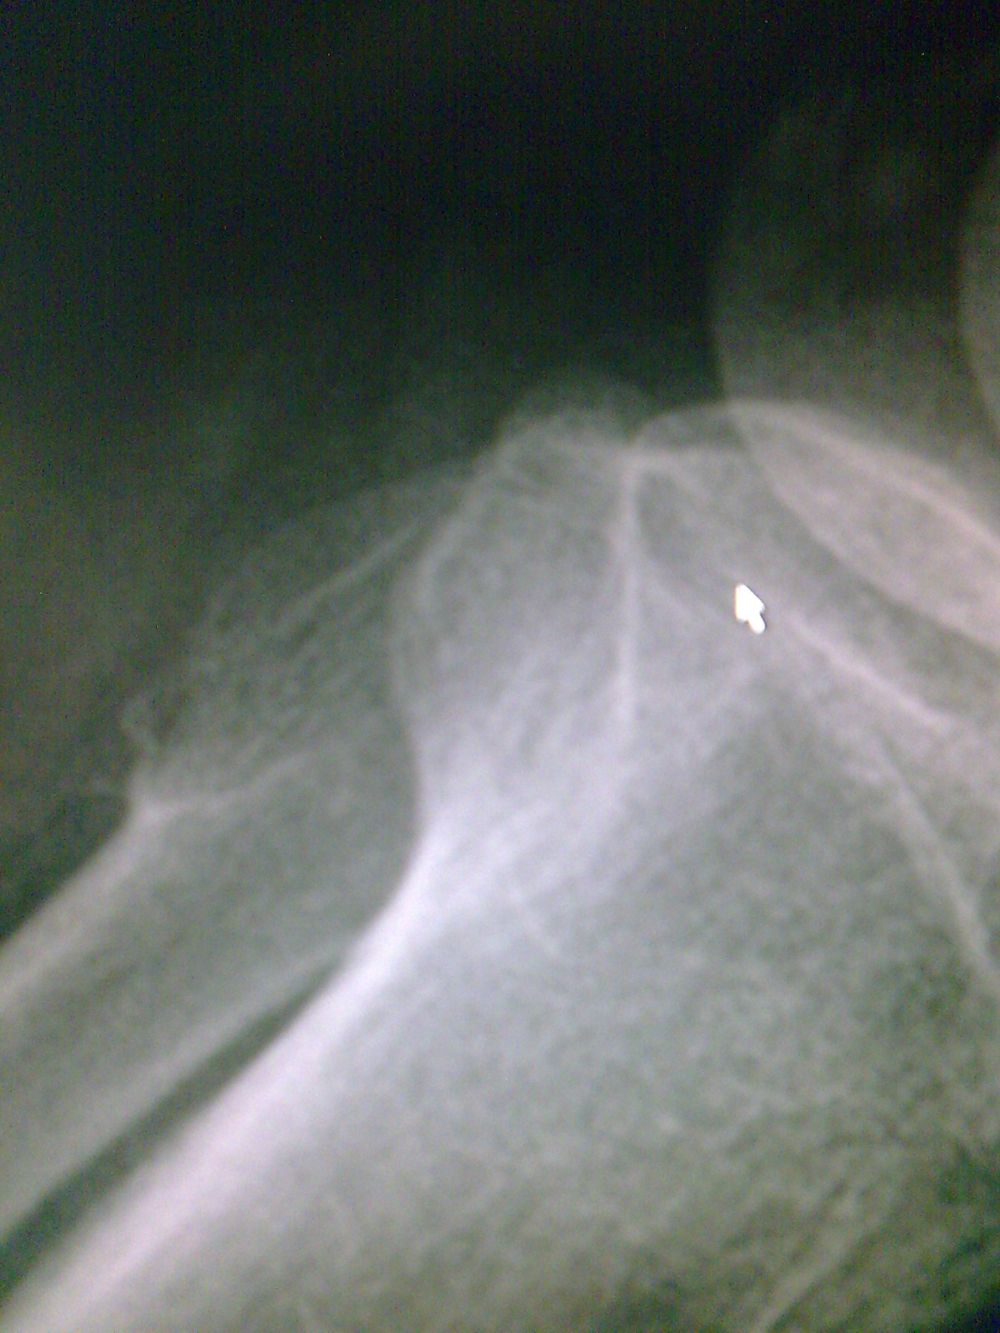

标题: CT19437:男性,四十岁,因外伤入院,X光平片发现腓骨近端 [打印本页]

标题: CT19437:男性,四十岁,因外伤入院,X光平片发现腓骨近端

建议除外骨肿瘤【典型骨肉瘤ct表现。1局部骨破坏,2骨膜反应,3周围软组织肿块;4,与骨膜肉瘤难区别】

kaolv 骨软骨瘤

考虑腓骨上端骨软骨瘤。

首先考虑比目鱼肌牵曳征,其次考虑骨软骨瘤。